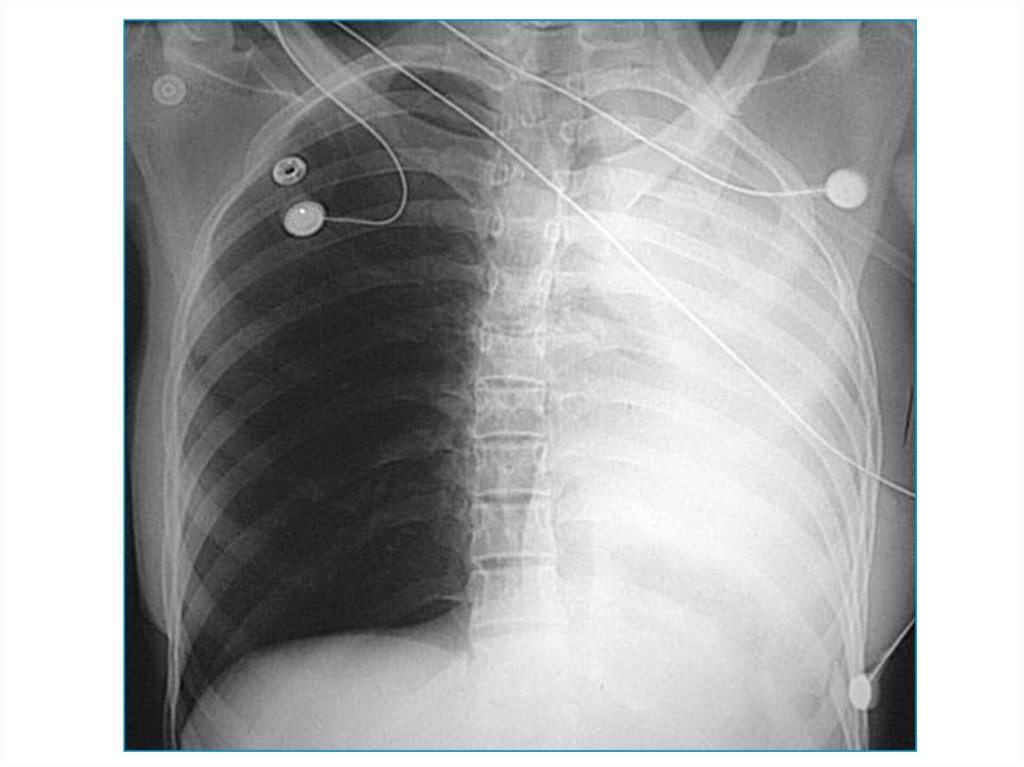

15. Наличие воздуха в плевральной полости

В большинстве случаев пневмоторакс - это

односторонний процесс. Может возникнуть в

результате травмы извне, либо спонтанно при

деструктивных процессах в легких. Имеет 3

механизма – открытый, закрытый, клапанный

(напряженный).

Видимая картина – поджатое к корню легкое,

смещение средостения в другую сторону.

Одностороннее просветление на стороне

поражения.

Напряженный пневмоторакс